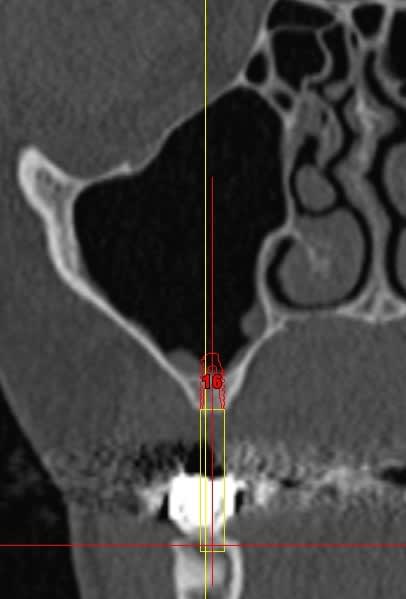

Pour l implant sur 14 il manque de l os en vestibulaire? Mise en place d os synthetique et membrane ou prelevement ramique?

Pour la 16 , une augmentation par abord lateral ou orthograde( desole je me souviens plus du nom de la technique).

Bonjour, pour la 16 ,tu peux faire une ostéotomie de SUmmers, tu as plus de 4 mm d'os .

Un implant de 10 mm devrait suffir.